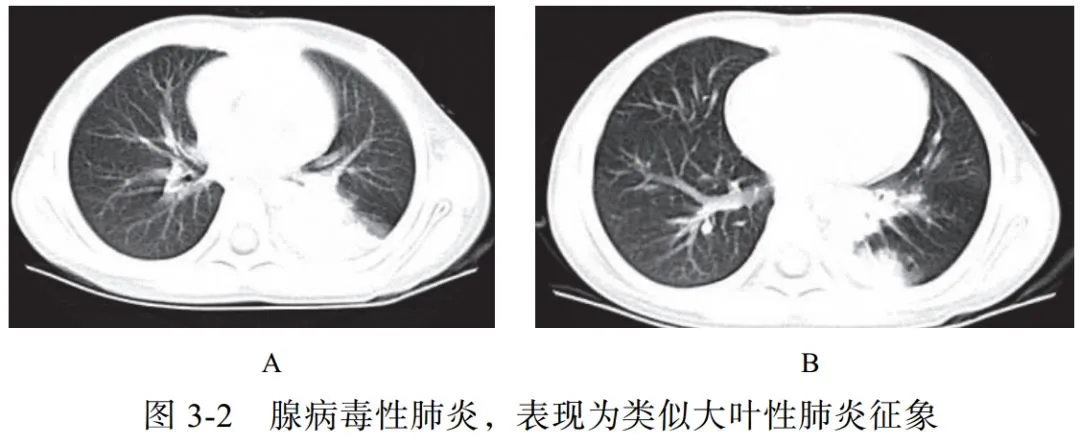

(二)腺病毒性肺炎

腺病毒属于哺乳动物腺病毒属,为无包膜的双链 DNA 病毒。腺病毒性肺炎易发生于婴幼儿或免疫功能障碍的人群。本病起病急,高热,并发症多

影像学表现:

(1)多呈大叶性分布(图 3-2A),实质、间质均受累

(2)可有空气潴留征、马赛克样灌注及肺气肿

(3)显示类似细菌性肺炎的支气管肺炎征象(肺叶或节段性分布),如腺泡结节、 GGO、实变等(图 3-2B)

(4)后遗症:闭塞性细支气管炎、支气管扩张、肺纤维化、单侧透明肺等